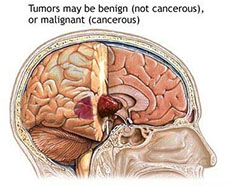

严重颅脑损伤、多发伤、复合伤

疾病介绍:严重颅脑损伤、多发伤、复合伤,多为交通、工矿事故、自然灾害、爆炸、火器伤、坠落、跌倒以及各种锐气、钝器对人体伤害。除正确诊断和及早手术外,加…【详细】